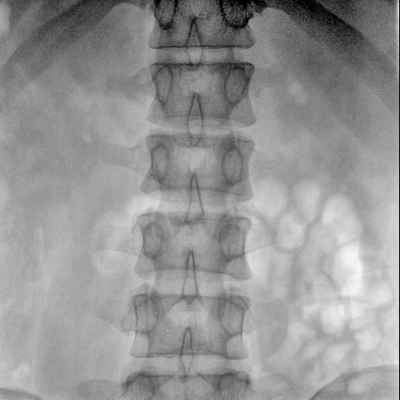

骨科: 經(jīng)皮錐體成形術(shù)、經(jīng)皮椎間盤臭氧治療術(shù)、胸脊椎固定、骨活檢、腰椎內(nèi)固定術(shù)等。

優(yōu)質(zhì)平板探測(cè)器、可靈活升降調(diào)節(jié)SID、獨(dú)特圖像處理系統(tǒng)、高品質(zhì)濾線柵,大視野成像清晰不失真。

采用智能劑量控制技術(shù),可根據(jù)不同體型和不同部位,準(zhǔn)確調(diào)節(jié)投照劑量。使操作者在任何使用環(huán)境下,都能實(shí)現(xiàn)低劑量、診視圖像清晰的效果。